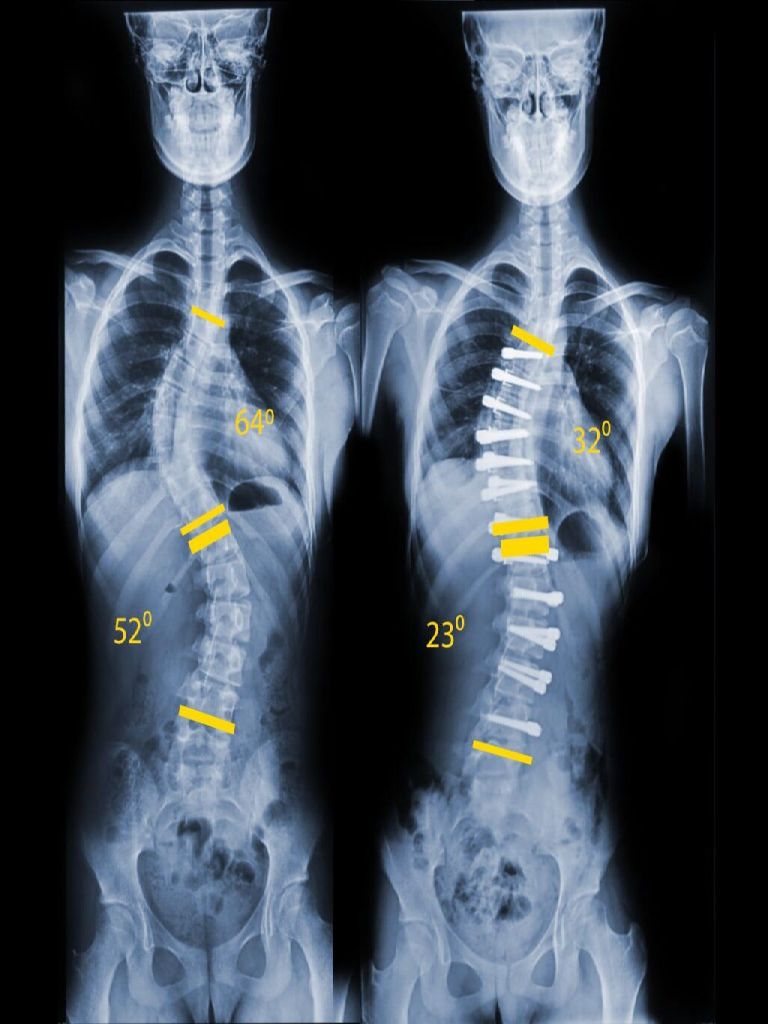

Детский сколиоз - не приговор